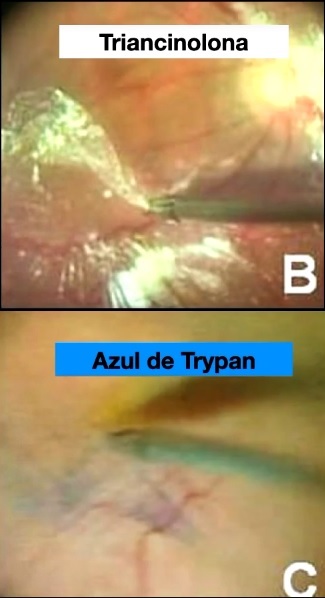

Quais são as substâncias utilizadas para identificação da MER durante a cirurgia de VVPP?

Triancinolona

Azul de Trypan